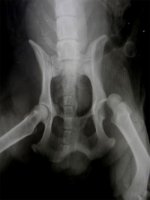

При радиографическом исследовании наиболее информативная проекция достигается, когда животное расположено на спине, а рентгеновские лучи направлены со стороны живота. Для получения более полной информации обычно добавляют снимки в боковой проекции.

При анализе снимков оцениваются конфигурация сустава, направление смещения головки бедра, отрыв ямки шейки бедра, целостность вертлужной впадины, наличие дисплазии тазобедренного сустава и сопутствующих поражений.

Рисунок 3. Радиографическая картина вывиха левого тазобедренного сустава (снизу). Собака была найдена волонтерами на дороге. После неудачной попытки закрытой репозиции была проведена открытая репозиция сустава с ушиванием капсулы синтетическим нерассасывающимся материалом (нейлоном). Исход благоприятный.